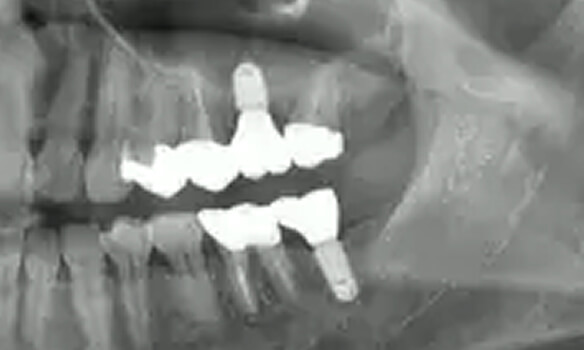

インプラント

という選択肢

歯を失った場合、自然な噛み心地を取り戻せる治療としてインプラントをご提案しています。周囲の歯に負担をかけず、見た目・機能ともにしっかり回復できる選択肢です。

04

抜歯になった際の

インプラントインプラントも対応

歯周病により破壊された、歯茎や骨を人工骨や成長因子などを用いて再生させる治療方法です。将来的に抜歯となるリスクの高い歯などを歯周組織を再生させ、歯を長持ちさせることを目的とします。歯周病でダメになった歯をどうしても残したい方、歯ぐきや歯槽骨を元に戻して歯の寿命をしっかり伸ばしたい方に適応される治療方法です。